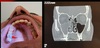

Q

Fenómeno de re circulación